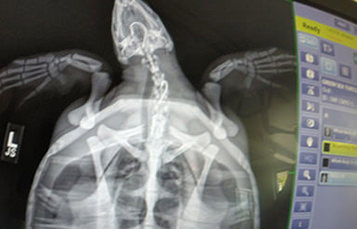

The surgical suite may include an x-ray machine, anesthesia equipment, a respirator unit, an ultrasound machine, and a surgery table.

Veterinarians sometimes also use specialized diagnostic equipment such as ultrasound machines and endoscopy equipment (scopes for seeing inside an animal's body).